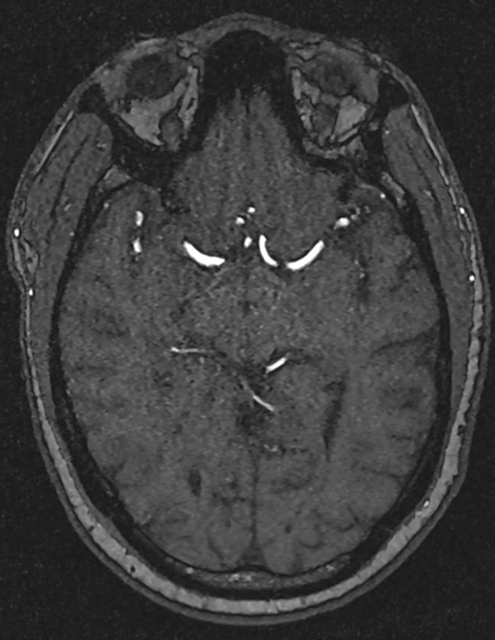

Le patient rapporte depuis trois semaines une diplopie lorsque ses deux yeux sont ouverts, qui disparaît à l’occlusion d’un œil. Il rapporte aussi une sensation d’instabilité à la marche avec une faiblesse de l’hémicorps gauche qui s’aggrave progressivement. Il ne décrit pas de sensation de rotation de lui-même ou de la pièce. Il a vu un ORL qui a prescrit un traitement symptomatique des vertiges, sans efficacité, raison pour laquelle il vous consulte.